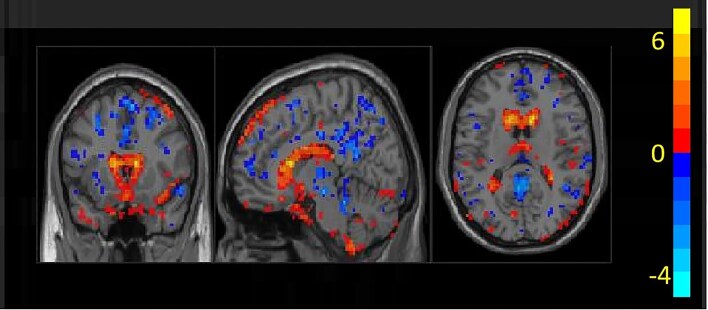

Materials and methods: The study included 27 patients with anti-LGI1 encephalitis and 28 age- and sex-matched normal controls. Amplitude of low-frequency fluctuation (ALFF) analysis identified altered brain regions. Spectral dynamic causal modeling (spDCM) then assessed EC between these regions. Relationships between EC strength and both clinical severity and cognitive function were analyzed.

Results: Distinct EC patterns were found in patients versus controls. Specifically, inhibitory EC was observed from the hippocampus to the superior temporal gyrus, while excitatory EC was noted in the reverse direction. Patients also showed reduced inhibitory self-connections in the posterior cingulate cortex. Crucially, inhibitory EC from the right hippocampus to the left superior temporal gyrus correlated inversely with symptom severity and positively with cognitive performance. Conversely, reduced inhibitory self-connections in the posterior cingulate cortex correlated positively with symptom severity and negatively with cognitive function.